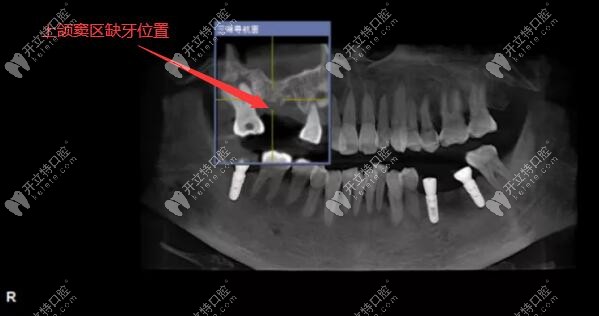

用3D數(shù)字化導(dǎo)板技術(shù)做上頜竇區(qū)的精準(zhǔn)種植牙案例

上頜竇外提升術(shù)人工種植牙發(fā)布時(shí)間: 2025-05-26

今日分享:用3D數(shù)字化導(dǎo)板技術(shù)做上頜竇區(qū)的精準(zhǔn)種植牙案例,植入的是美國皓圣3508和4507型號的種植體。